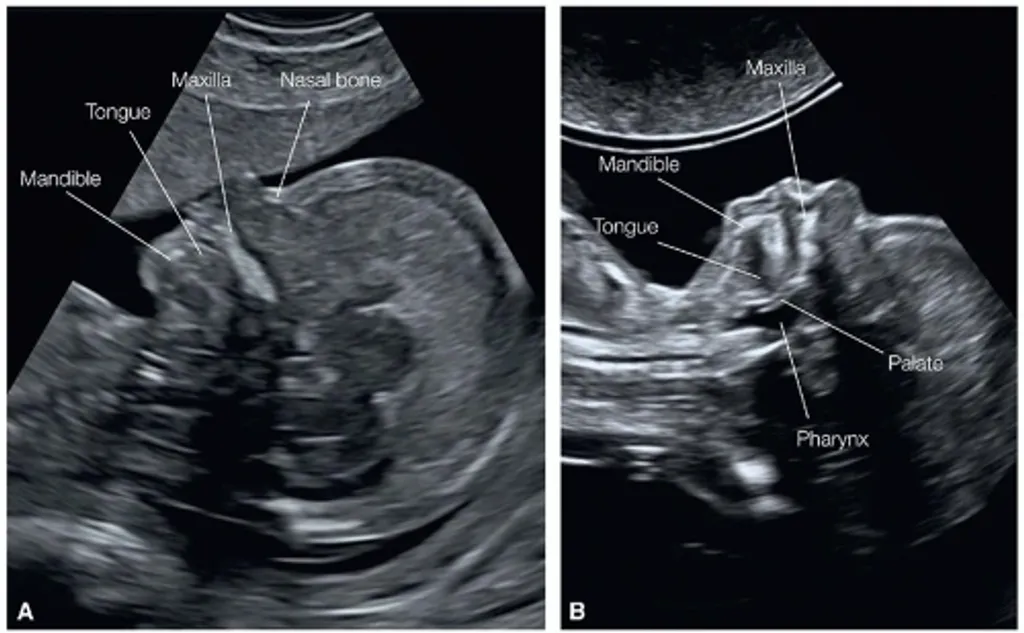

• nasal ബോൺ: ഈ സ്കാനിൽ കുഞ്ഞിന് nasal ബോൺ ഉണ്ടോ എന്നും നോക്കാം. അത് കാണാതിരിക്കുന്നതും ഒരു സൂചനയായി കണക്കാക്കപ്പെടുന്നു.

• മുഖം: ചുണ്ട്, അണ്ണാക്ക് എന്നിവയിൽ എന്തെങ്കിലും പ്രശ്നങ്ങളുണ്ടോ എന്ന് പരിശോധിക്കുന്നു.